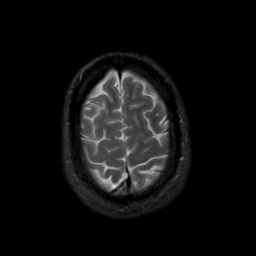

MR Study #16, June 23, 1991 -- Slice #43

[Home][Help][Clinical][Tour 1][Tour 2] Slice 43